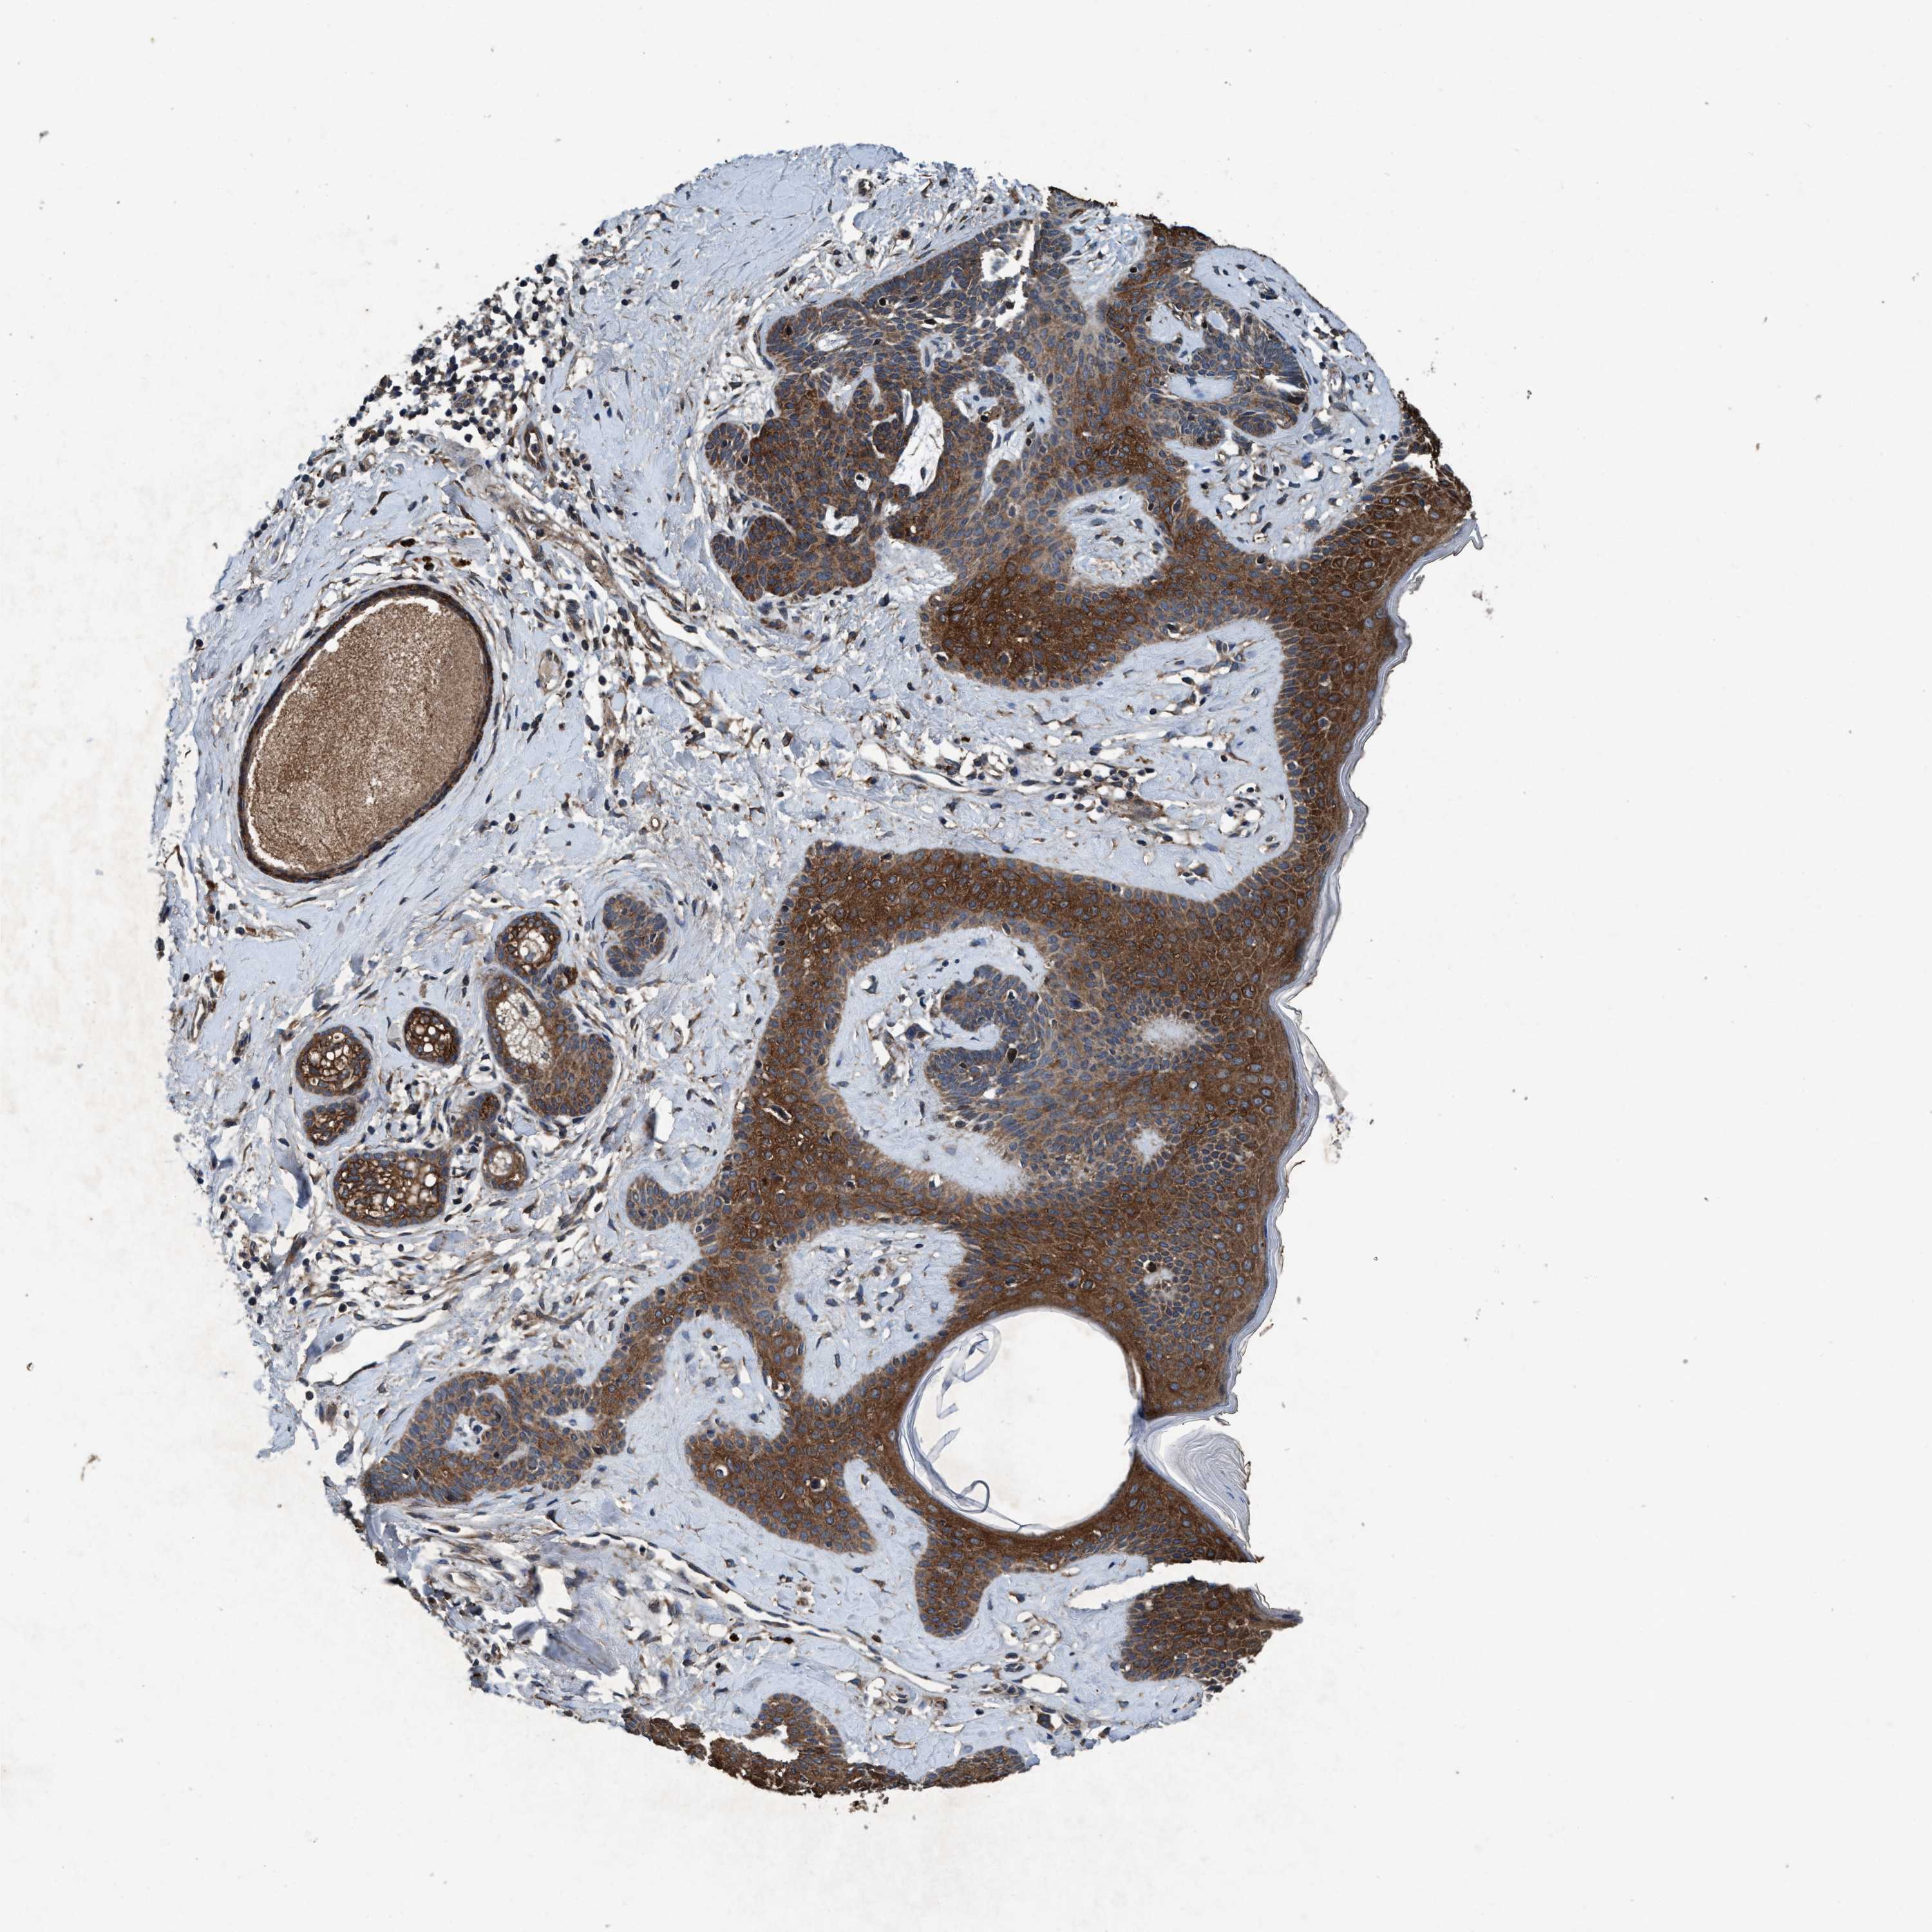

SKIN CANCER - Protein expressioni

A mouse-over function shows sample information and annotation data. Click on an image to view it in a full screen mode. Samples can be filtered based on level of antibody staining by selecting one or several of the following categories: high, medium, low and not detected. The assay and annotation is described here.

Each image is clickable and will lead to virtual microscopy that enables deeper exploration of all samples and also displays staining intensity scores, fraction scores and subcellular localization as well as patient and tissue information for each sample.

Antibody HPA064427

Antibody CAB021903

Staining

High

Medium

Low

Not detected

Intensity

Strong

Moderate

Weak

Negative

Quantity

>75%

75%-25%

<25%

None

Location

Nuclear

Cytoplasmic/membranous

Cytoplasmic/membranous,nuclear

Basal cell carcinoma

BCC, high aggressive

Squamous cell carcinoma, NOS